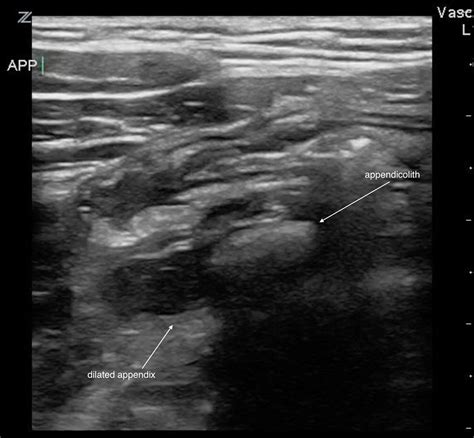

When performing an ultrasound to diagnose appendicitis, radiologists look for several key signs:

• Appendicoliths: These are small, calcified stones that can be seen within the appendix on ultrasound. Their presence can indicate a higher risk of appendicitis.

• Periappendiceal Fluid: The presence of fluid around the appendix can indicate inflammation or infection.